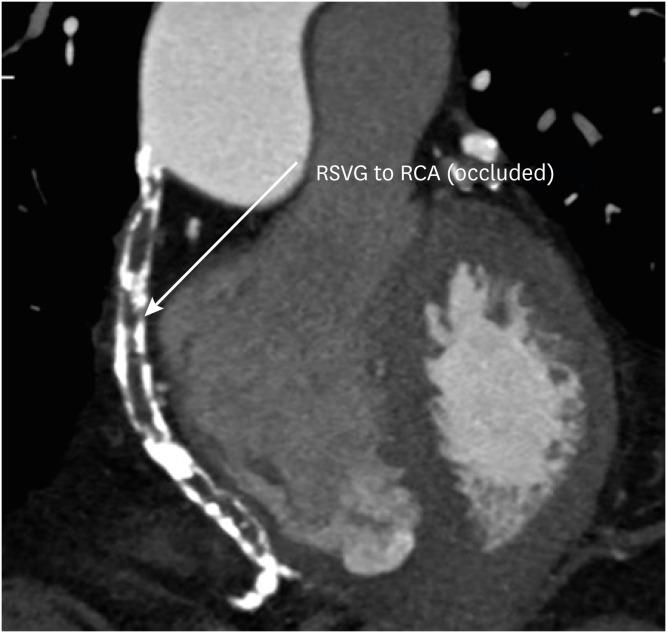

冠状动脉疾病报告与数据系统:全面综述。

Coronary Artery Disease Reporting and Data System: A Comprehensive Review.

The Coronary Artery Disease Reporting and Data System (CAD-RADS) is a standardized reporting method for coronary computed tomography angiography (CCTA). It summarizes the findings of CCTA in 6 categories ranging from CAD-RADS 0 (complete absence of coronary artery disease) to CAD-RADS 5 (total occlusion of at least one vessel). It is applied on per patient basis for the highest grade of the stenotic lesion. The CAD-RADS also provides category-specific treatment recommendations, helping patient management. The main objectives of the CAD-RADS are to improve the consistency in reporting, facilitate the communication between interpreting and referring clinicians, recommend the best course of patient management, and produce consistent data for quality improvement, research and education. However, CAD-RADS has many limitations, resulting into the misclassification of the observed findings, misinterpretation of the final category, and misguidance for the treatment based upon the single score. In this review, the authors discuss the CAD-RADS categories and modifiers, along with the strengths and limitations of this new classification system.

冠状动脉疾病报告与数据系统(CAD-RADS)是一种用于冠状动脉计算机断层扫描血管造影(CCTA)的标准化报告方法。它将CCTA的结果总结为6类,范围从CAD-RADS 0(完全不存在冠状动脉疾病)到CAD-RADS 5(至少一根血管完全闭塞)。它针对每位患者应用于狭窄病变的最高等级。CAD-RADS还提供特定类别的治疗建议,有助于患者管理。CAD-RADS的主要目标是提高报告的一致性,促进解读医生与转诊医生之间的沟通,推荐最佳的患者管理方案,并产生用于质量改进、研究和教育的一致数据。然而,CAD-RADS有许多局限性,导致观察结果的错误分类、最终类别的错误解读以及基于单一分数的治疗误导。在本综述中,作者讨论了CAD-RADS类别和修饰符,以及这个新分类系统的优点和局限性。